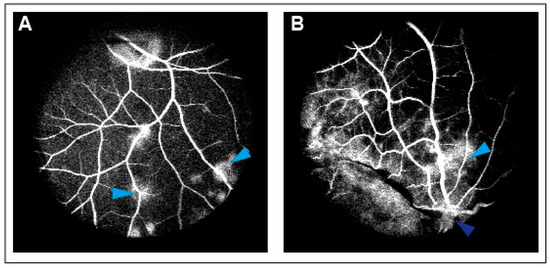

An intravitreal injection of 0.05 mL bevacizumab 25 mg/mL (Avastin; Roche, Copenhagen, Denmark) was injected into the right eyes of the animals (n = 9), while an intravitreal injection of 0.05 mL sodium chloride 9 mg/mL (NaCl) (B. Braun, Denmark) was given to the left control eyes (n = 9). Successfully induced CRVO was confirmed by angiography 4 days after the induction of CRVO.

CRVO was successfully induced in all eyes (Figure 1). Angiography confirmed successfully induced CRVO (Figure 2).

Figure 2. (A) Leakage of fluorescein observed following CRVO. Light blue arrow: Leakage of fluorescein. (B) Leakage of fluorescein upstream of the occlusion site. Light blue arrow: Leakage of fluorescein. Dark blue arrow: Site of occlusion.